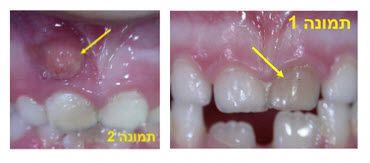

שינוי הצבע במקרה זה ייראה, בדרך כלל, זמן קצר אחרי שהשן קיבלה מכה (תמונה 1). בדיוק כמו במקרים של שטף דם בגוף (שהופך מכחול לסגול עד שנעלם), כך יכול לקרות גם בשן, אשר תחזור בסוף לצבע בהיר.

גם אתם, ההורים, יכולים לשים לב לזיהום אם החניכיים מעל השן האפורה הפכו אדומים, נפוחים, או שנראית בהם בליטה (תמונה 2). במקרה כזה עליכם לגשת בהקדם לרופא השיניים שיחליט האם ניתן להציל את השן בעזרת טיפול שורש או עקירה.